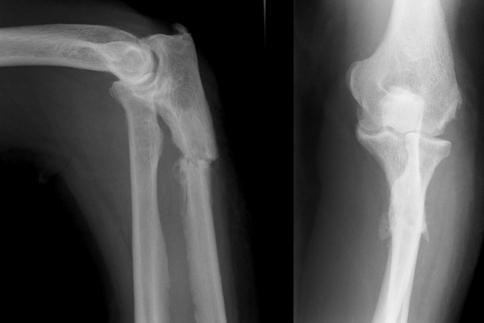

A 60-year-old left hand-dominant woman presented 3 days after hearing a crack in the left forearm whilst taking her jumper off. She had subsequently noticed pain and swelling at this site. There was no history of preceding trauma. Relevant past medical history included severe osteoarthritis of the hips, knees and back requiring below elbow crutches to mobilise. She was taking non-steroidal anti-inflammatory medications for pain relief. On examination, there was diffuse swelling over the proximal ulna associated with tenderness over the site. Plain radiographs (Fig. 1) showed an undisplaced transverse fracture through the proximal metaphysis of the ulna. She was treated conservatively and provided with alternative crutches to avoid weight bearing on the forearm.

Fig. 1.

Anterior-posterior (AP) and lateral plain radiographs demonstrate a transverse fracture through the proximal metaphysis of the ulna